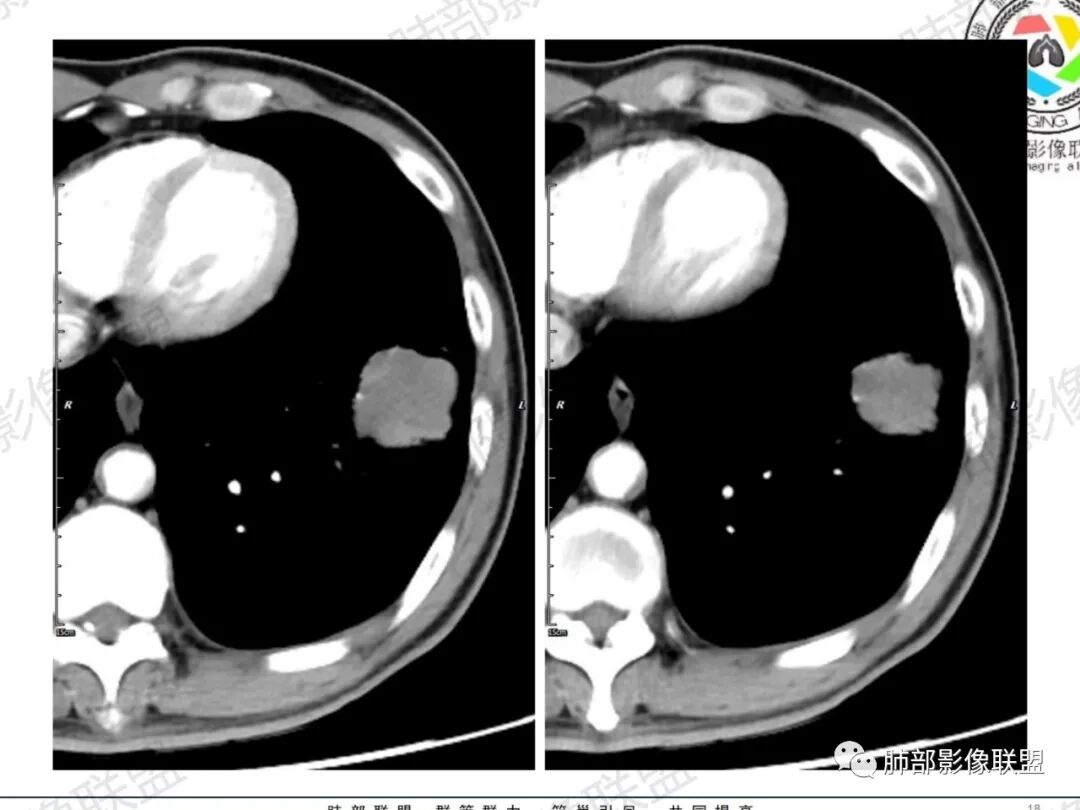

一切∮随缘:左肺下叶不规则肿块,边缘光滑,平直,局部彭隆,分叶,近端支气管堵塞,远端与胸膜相贴,平扫密度尚均匀,增强后不均匀强化,内部可见低密度坏死,胸膜下多发肺气肿,伴双肺散在光滑小结节,实验室肿瘤标志物高,考虑恶性:神经内分泌癌(大细胞),腺癌,鳞癌。

琦遇:恶性没有问题,肺气肿底子、病灶分叶、少许毛刺、叶间胸膜凹陷、部分边缘可见清晰的GGO、胸膜牵拉凹陷、局部胸水、近端支气管截断、部分支气管被推移、占位效应明显、强化特点为不均匀强化、内部有少许沼泽样低强化区,强化部分轻中强化为主、余肺可见转移性结节、左肺上叶似为囊腔型腺癌一枚,肿瘤标志物提示非小、神经内分泌,综合分析考虑大神泌、腺癌、腺鳞癌、鳞癌  同时左肺上叶囊腔型腺癌  肺转移

飞鹰行动:中年人,男性,胸疼入院,左肺下叶占位,张力较高,边界可见分叶,局部可见明显收缩性改变,增强病灶内部有延迟强化表现,考虑恶性病变,大细胞癌伴肺内转移或者囊腔样腺癌伴转移。

蕊:中老年男性,吸烟史,肺气肿背景,左肺上叶类圆形肿块影,边界清晰,边缘凹凸不平,有分叶,支气管进入阻断,临近胸膜栽赃,整体病灶膨隆,局部周围可以清晰ggo,临近叶间裂内凹,轻度强化,并可见多个低密度区,坏死可能,界线不清;肺内多结节,边缘光滑,考虑恶性伴转移,鳞癌、腺癌

傅昌瑜:中老年男性,肺气肿背景,右胸背疼痛1周。CEA、NSE、CYFRA—211升高。左上肺混合磨玻璃结节,内见较多空泡和扩张支气管。左下肺胸膜下肿块,边缘较光滑,深分叶,似有血管进入,与支气管关系不清,内见不均匀强化,见沼泽地样坏死,有胸膜栽赃。另两肺多发圆形小结节。考虑恶性并肺内转移,多原发可能性大,左上肺腺癌,左下肺病理难以判断,小细胞癌?鳞癌?

小锁:中老年男性,肺气肿背景,右胸背疼痛1周。CEA、NSE、CYFRA—211升高。左上肺混合磨玻璃结节,边界清楚,内见较多空泡。左下肺肿块,边缘清楚,深分叶,有血管和支气管进入,胸膜凹陷。另两肺多发圆形小结节。考虑双发原位癌,左上肺腺癌,左下肺大神泌或腺鳞癌可能,肺内转移。

蓝天白云:中年男性,肺气肿背景,左肺下叶肿块,边缘膨隆,有分叶,内有湖泊样坏死,有轻中度强化,局部胸膜栽赃,收缩力不强,周围见肺气肿征象。左肺上叶混合磨玻璃影,边界清楚,考虑都是恶性,左上肺iac,左下肺腺鳞癌,或大细胞肺癌可能。两肺多发结节,考虑转移

毛勤香:老年男性,肺气肿背景,左肺下叶肿块,分叶,边缘光滑,土豆块样,细支气管闭塞,增强轻度不均匀强化,似有坏死,左肺另见多发结节,淋巴结未见明显肿大,恶性确定,吸烟史,鳞癌破坏力强,侵袭力差,多原发的一般很少多于3个,故排后,首先考虑神经内分泌癌,局部血管穿行,鉴别淋巴瘤

周太狼:中年男性,吸烟、高血压史,肿瘤指标升高,肺气肿背景下,左肺下叶肿块影,分叶、膨隆、未跨叶裂,支气管截断,不均匀强化。另双肺多发结节及磨玻璃影,左肺上叶混合磨玻璃,内可见多发空泡影。整体考虑恶性,肺癌伴肺内转移,左下肺鳞癌?神经内分泌癌?左肺上叶囊腔腺癌?